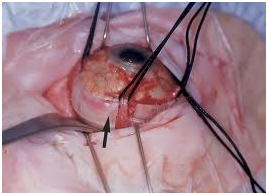

Retinal Detachment Surgery by putting silicon buckle

Vitroretinal Surgery